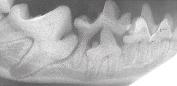

Dental x-rays (or radiography) allow us to "look underneath" the gum line for disease and infection. It helps us, just like your dentist, to provide better care and treatment options.

One of these canine teeth (fangs) has dental disease that is not visible without an X-ray. Which one?

The x-ray below shows an infection at the root of the fang on the left.